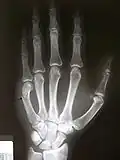

- Frattura del pugilatore - Una frattura del collo metacarpale (o frattura sottocapitale del metacarpo) è comunemente detta frattura del pugile, poiché sono causate dal colpire un oggetto duro[87]. Allorché non si abbia cura di colpire direttamente per tramite del 2° e del 3° metacarpo (corrispondenti alle dita: indice e medio, i più robusti), e si colpisca invece di striscio con il 4° od il 5° (corrispondenti alle dita: anulare e mignolo), può capitare di fratturarsi la mano[88][89]. Qualora la frattura sia dovuta ad un colpo dato a mano nuda, presso la bocca di qualcun altro, la cute potrebbe rimanere lacerata. La contaminazione della ferita cutanea con batteri orali può causare lesioni infettive tali da compromettere permanentemente la funzionalità della mano stessa, se non tempestivamente curate[87].

- Sintomi: nocche gonfie o doloranti, dita in posizione anomala.

- Diagnosi: clinica, ma comunque necessaria una radiografia.

- Cura: si prevede l'immobilizzazione tramite tutore, oppure può rendersi necessario un intervento chirurgico (dipende se v'è presenza di disallineamento o rotazione nei tronconi); per poi procedere con esercizi di mobilizzazione[87].

- Prognosi: generalmente buona se c'è stato buon esito nei vari passaggi fra chirurgo e medico familiare[90]. Tuttavia in caso di frattura malconsolidata (provocante dolore, difficoltà motoria, spostamento alle dita) occorre intervenire tramite un'osteotomia correttiva, un tipo di intervento piuttosto impegnativo.[90]